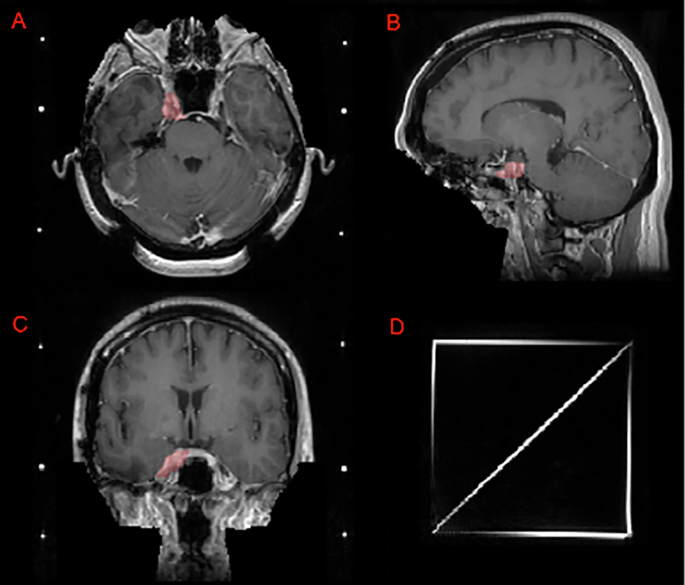

Image panels depicting a case that utilizes a SRS planning Gamma Knife headframe. Panels A, B, and C depict an intact meningioma (red) in the right Meckel’s cave on T1c axial, sagittal, and coronal images, respectively. Note that this challenge’s defacing technique preserves this meningioma as compared to a skull-stripping pre-processing technique which would have excluded at least part of this lesion. Panel D shows the SRS localizer box fiducials attached to a standard Gamma Knife headframe.